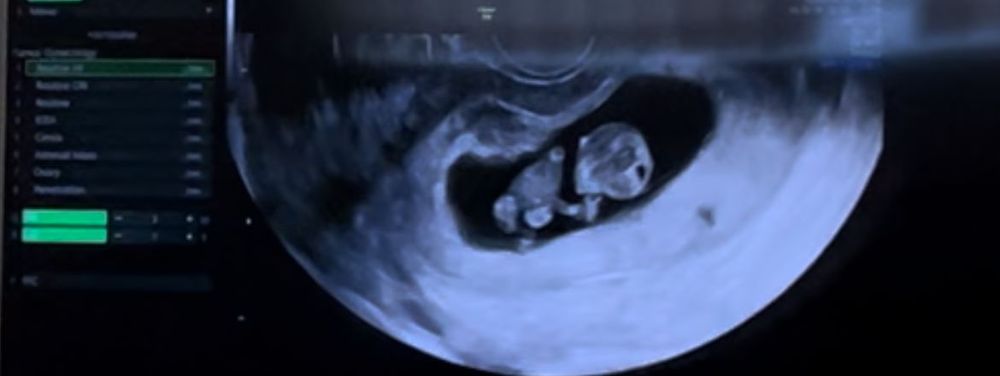

Делала в 10 ) была в шоке, когда увидела на экране пупсика, уже ножками ручками шевелил 🥰 одна из самых ярких эмоций за всю беременность 😭 смотрели и так, и так.

Конечно похож ) я делала УЗИ в 9 недель + 1 день - уже был маленький человек. Махал руками/ногами, отталкивался от стенок матки. Мне смотрели и внутренним и абдоминальным датчиком. Теперь иду на 11 недель + 5 дней.

Делала в 8н+4д вполне себе 2х сантиметровый человечек) со всеми конечностями, шевелится) делали трансабдоминально